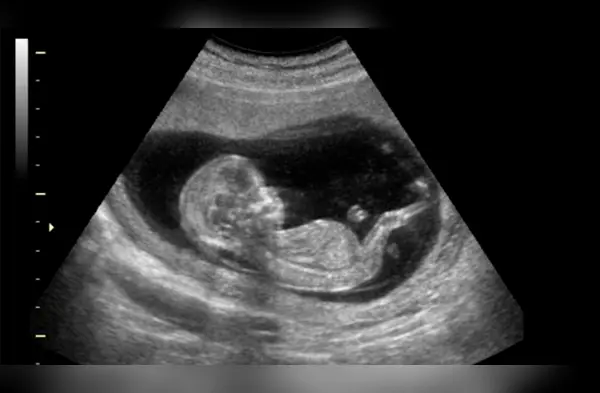

Eso podría explicar la sorpresa que este bebé les dio a sus padres. La mujer junto a su esposo se estaba sometiendo a una ecografía a las 28 semanas cuando al parecer el feto los estaba saludando, la pareja no podía creer lo que estaba pasando.

En el clip se aprecia en un momento el feto girando hacia la “cámara” y empieza a agitar una de sus manitas como si estuviera saludando a sus papás. El doctor quedó impresionado ante las imágenes ya que él comenta que nunca le había pasado eso.